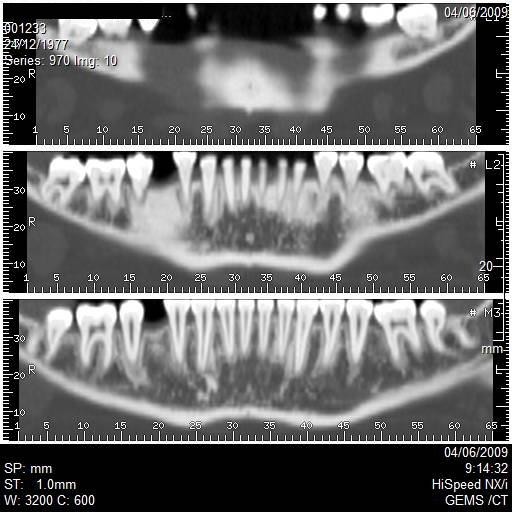

Los implantes óseo-integrados se han convertido en una forma aceptada de reemplazo dental permanente. Un importante avance en la evaluación preoperatoria de los candidatos para colocación de implantes es el desarrollo de un software para escanografia que es capaz de generar imágenes panorámicas y axiales del maxilar superior y de la mandíbula. Estas imágenes permiten al Odontólogo Implantólogo realizar varias medidas para determinar si el sitio es adecuado para la colocación de un implante.

Incluye la altura, ancho y angulación del reborde alveolar; calidad del hueso en el sitio del implante; relación del sitio del implante con las estructuras adyacentes como son el reborde alveolar, canal mandibular y foramen mentoneano en la mandíbula y el reborde alveolar, la fosa nasal, el seno maxilar y el ducto nasopalatino en el maxilar superior. La medición por escanografía es un método muy exacto de planeación permitiendo así una adecuada óseo integración del implante que ayuda al éxito del mismo.